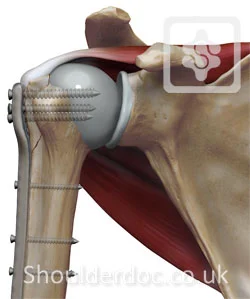

Surgical Neck- Problem

- If osteoporotic bone

- Difficult fixation

- Possible associated injury to Axillary nerve

- Motor: Deltoid

- Sensory: upper lateral arm